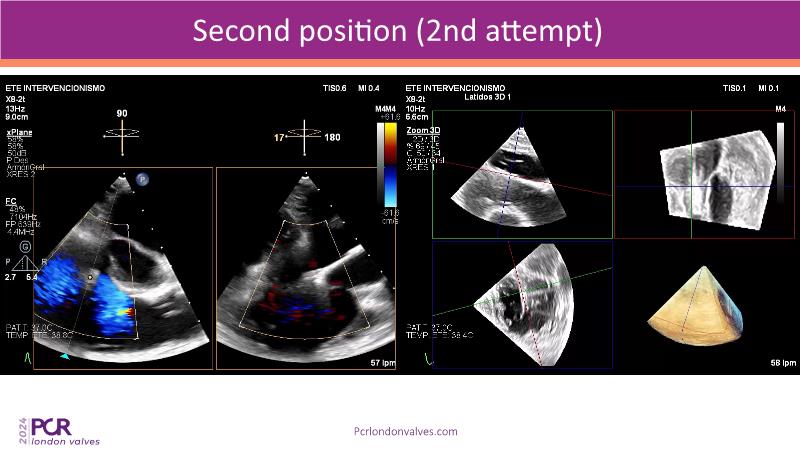

This session examines two compelling cases: a 78-year-old woman with paroxysmal atrial fibrillation, chest trauma, an osteoporotic sternum fracture, and NYHA II exertional dyspnoea, and an 82-year-old man with chronic three-vessel coronary artery disease, bradycardic AF, peripheral arterial disease, spinal stenosis, and chronic kidney disease. Through their study, discover the intricate anatomy of atrioventricular valves, the therapeutic challenges they pose, and the growing significance of transcatheter edge-to-edge repair (TEER) therapies. The discussion also highlights the value of multidisciplinary strategies in managing complex valve diseases effectively.